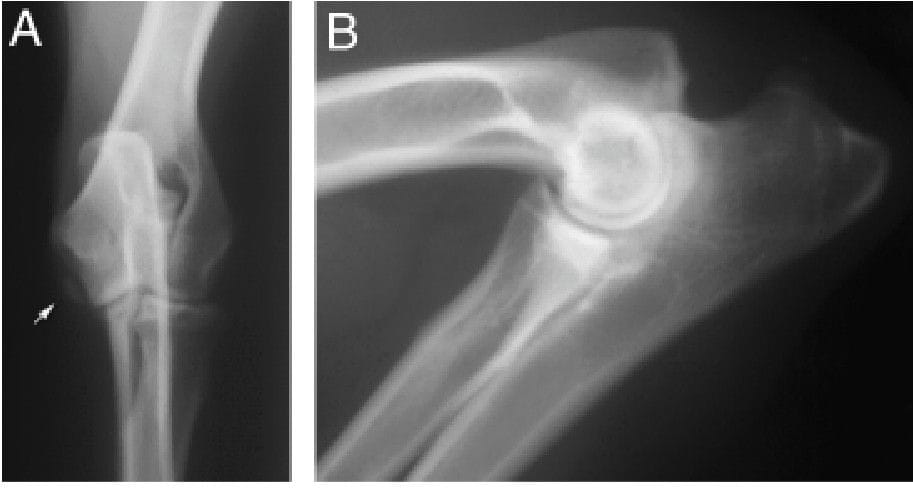

Craniocaudal (A) and extreme flexed mediolateral (B)radiographic projections of an elbow in a dog with un-unitedmedial epicondyle (UME) is shown. The UME fragment isseen on the craniocaudal, but not the flexed mediolateral pro-jection.171PASTER ET AL

UME occurred in 15% of this Labrador Retriever cohort and was predominantly unilateral. The craniocaudal radiographic projection was essential for diagnosis, whereas the flexed lateral projection alone frequently failed to identify lesions. No significant association was found between UME and elbow OA, and no concurrent components of elbow dysplasia were identified. These findings suggest that UME may be more prevalent than previously recognized and is unlikely to represent a component of the elbow dysplasia complex, although further genetic and larger-scale studies are warranted.